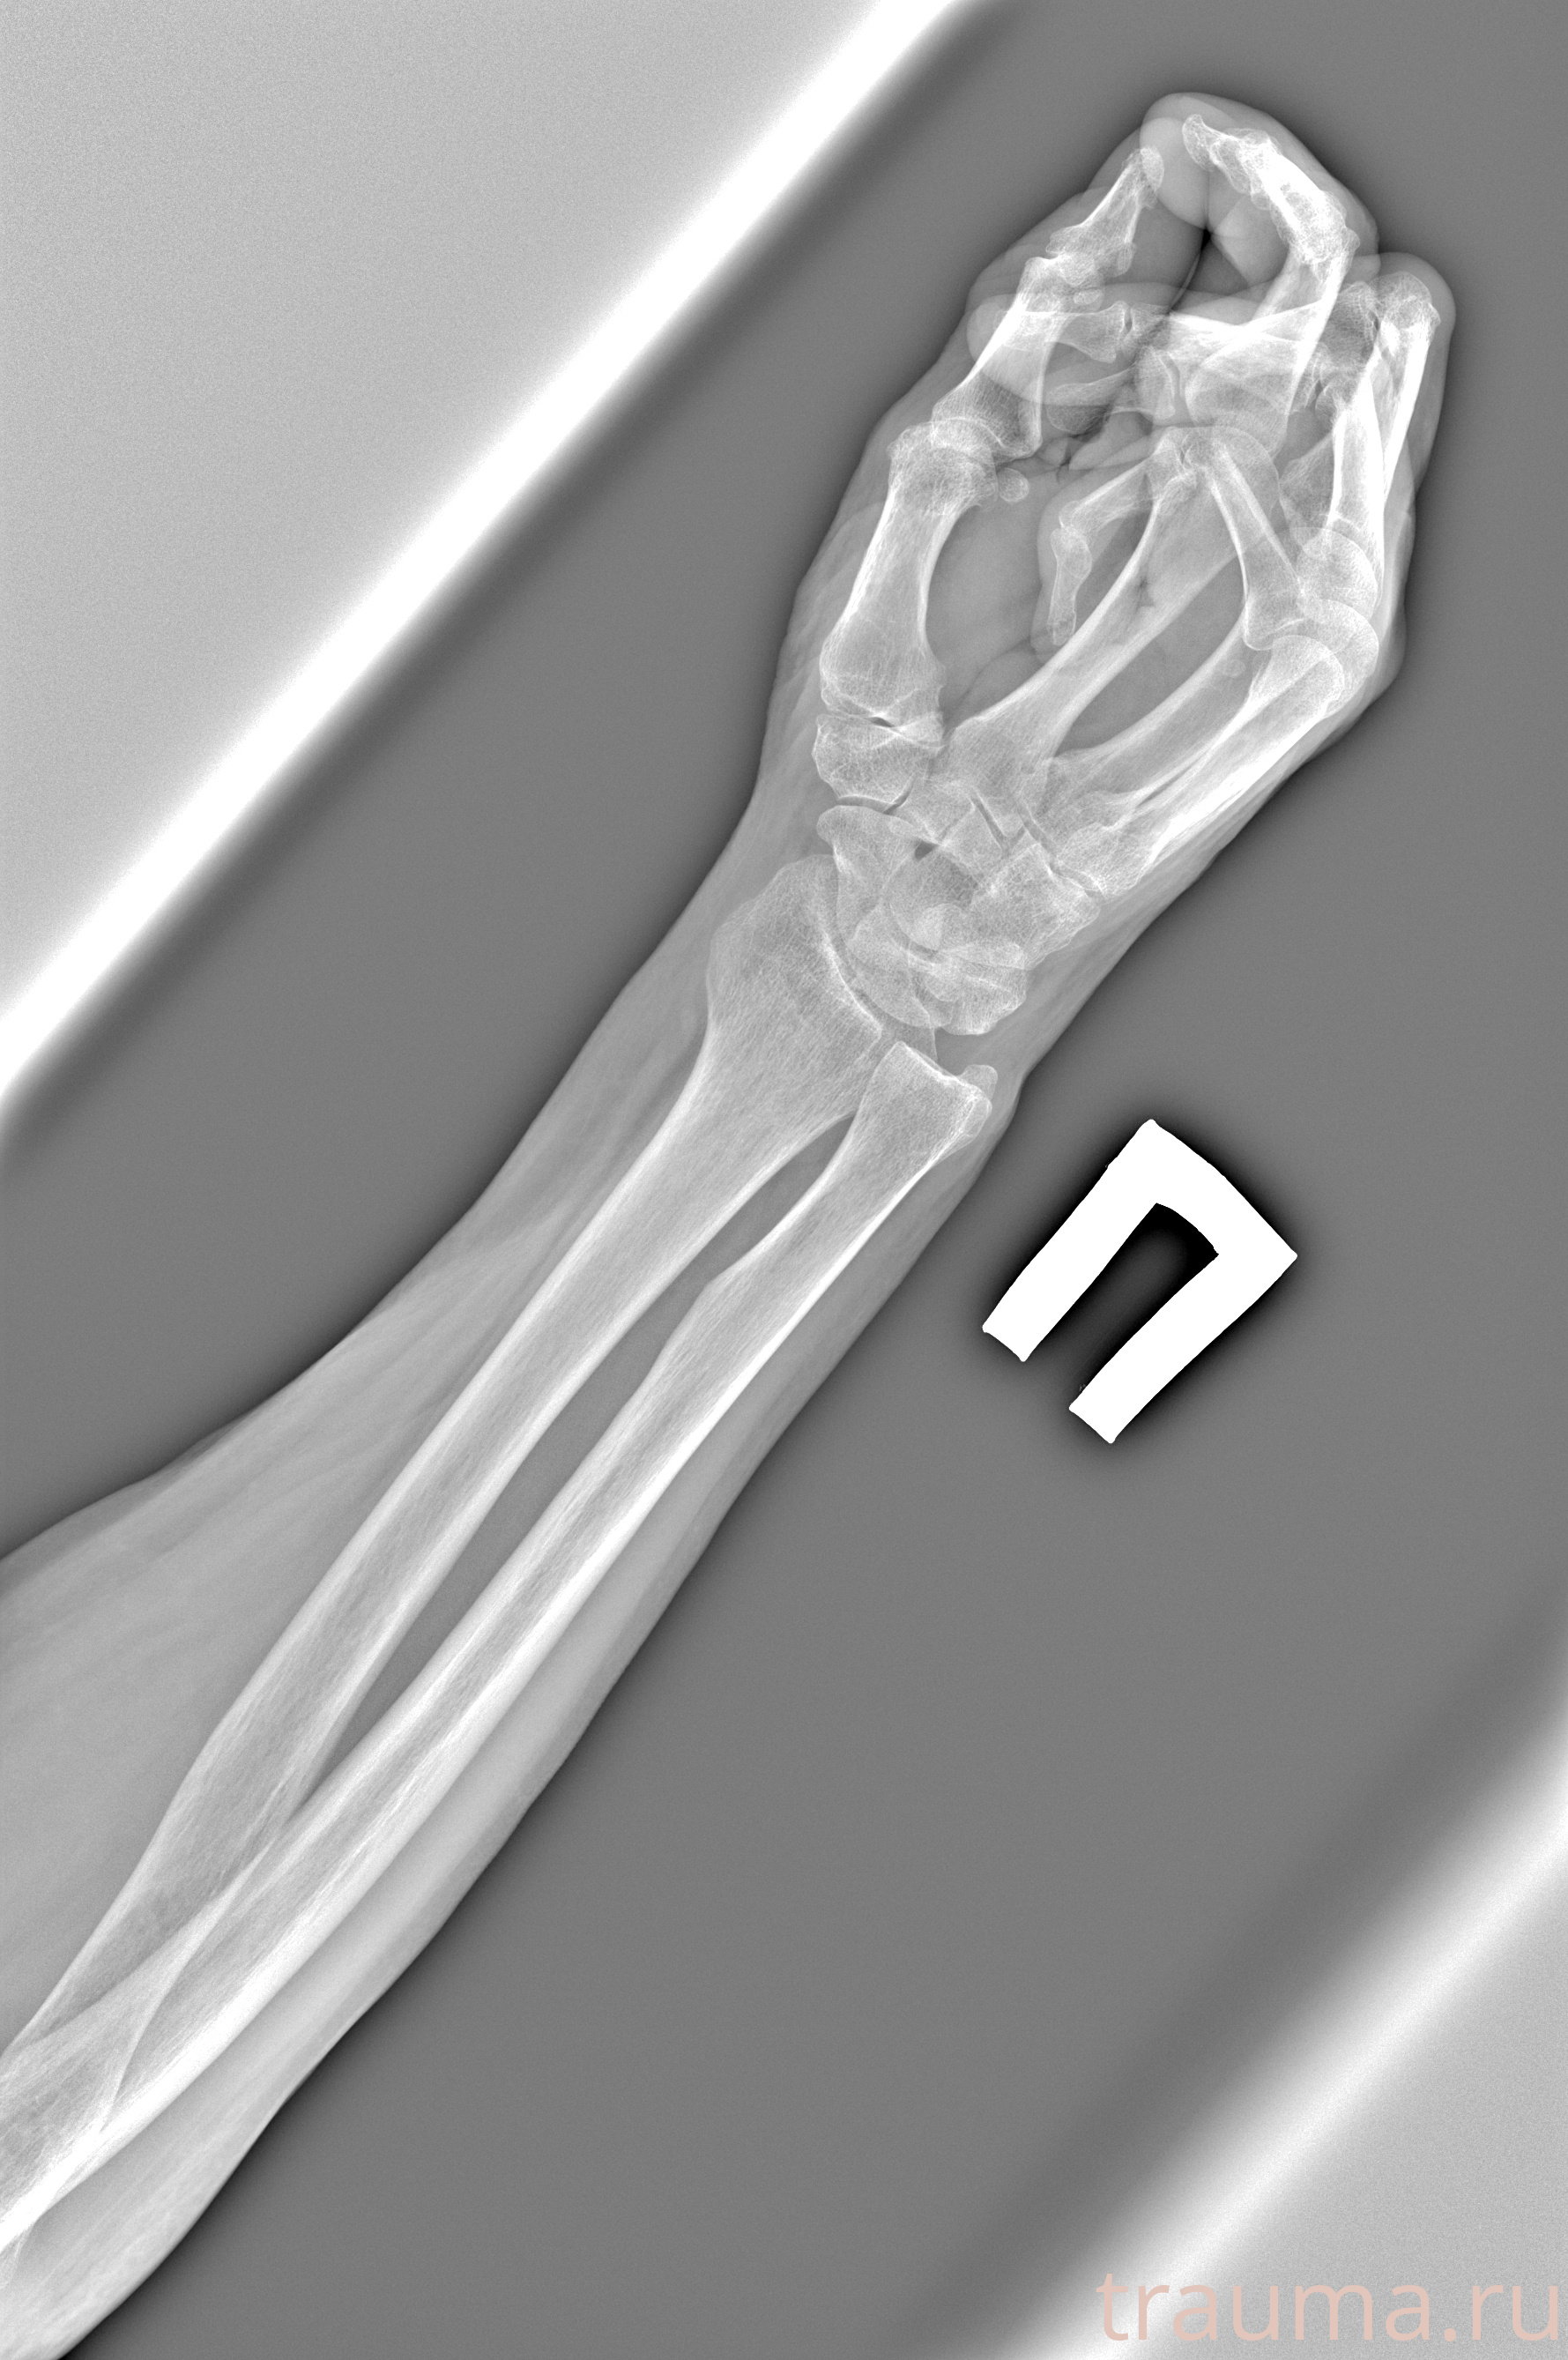

Рентген на дому: по вашему адресу приезжает врач-рентгенолог, травматолог-ортопед с мобильным рентгеновским аппаратом, проводит диагностику травмы или заболевания, делает необходимые рентгенограммы, дает рекомендации по дальнейшему лечению. Получить качественные снимки в домашних условиях возможно благодаря уникальной методике, разработанной МосРентген Центром для института  Склифосовского